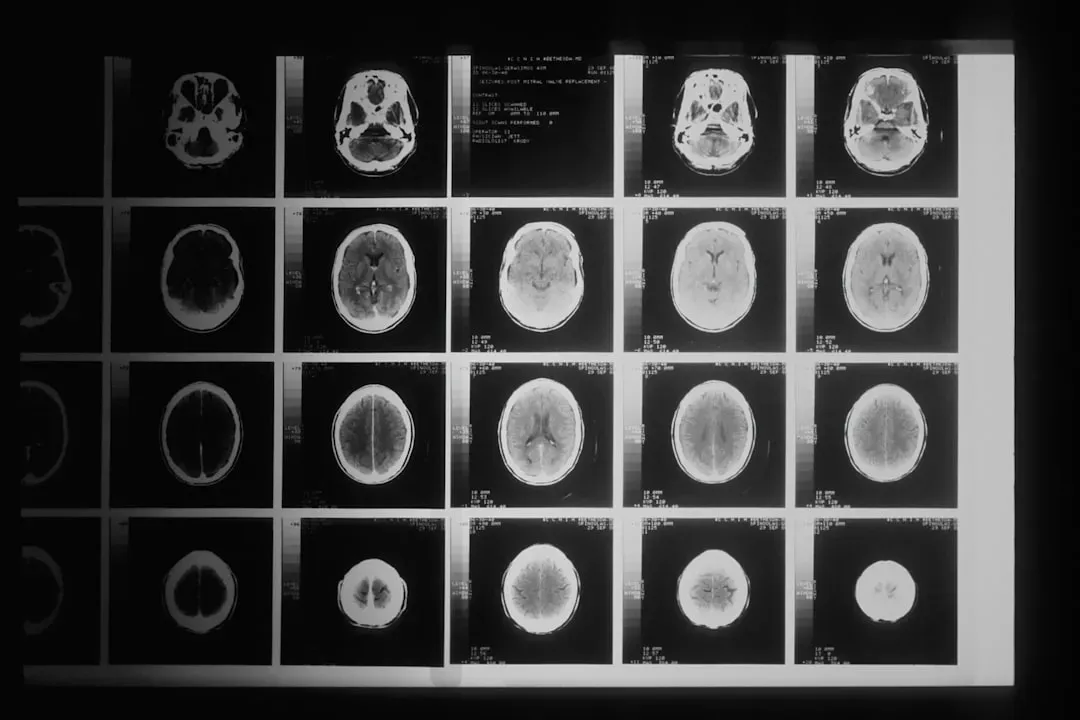

Every night, as you fall asleep, your brain doesn’t shut down; it shifts into a complex rhythm of stages that repeat in cycles, like a slowly turning carousel. Scientists usually describe these as light sleep, deep sleep, and rapid eye movement, or REM sleep, and that last one is where most vivid, story-like dreams happen. During REM, your brain activity can look surprisingly similar to when you’re awake, especially in areas linked to vision and emotion, even though your muscles are effectively paralyzed so you don’t act out what you’re dreaming. It’s almost like your brain sneaks off to run a private simulation while your body is safely “locked” in place.

With brain imaging tools, such as functional MRI and EEG, researchers can see which regions light up across the sleep cycle. Some of the older, more purely symbolic theories don’t hold up well when compared with this data, especially the idea that there’s a single, fixed “dictionary” of dream symbols. Instead, interpretations tend to be more personal and tied to your experiences and concerns. There’s still room for meaning, but it’s grounded less in universal codes and more in how your own brain organizes thoughts and feelings. In a way, the modern view is less mystical but more intimate: your dreams reflect the way your unique brain is wired and what it’s currently wrestling with.